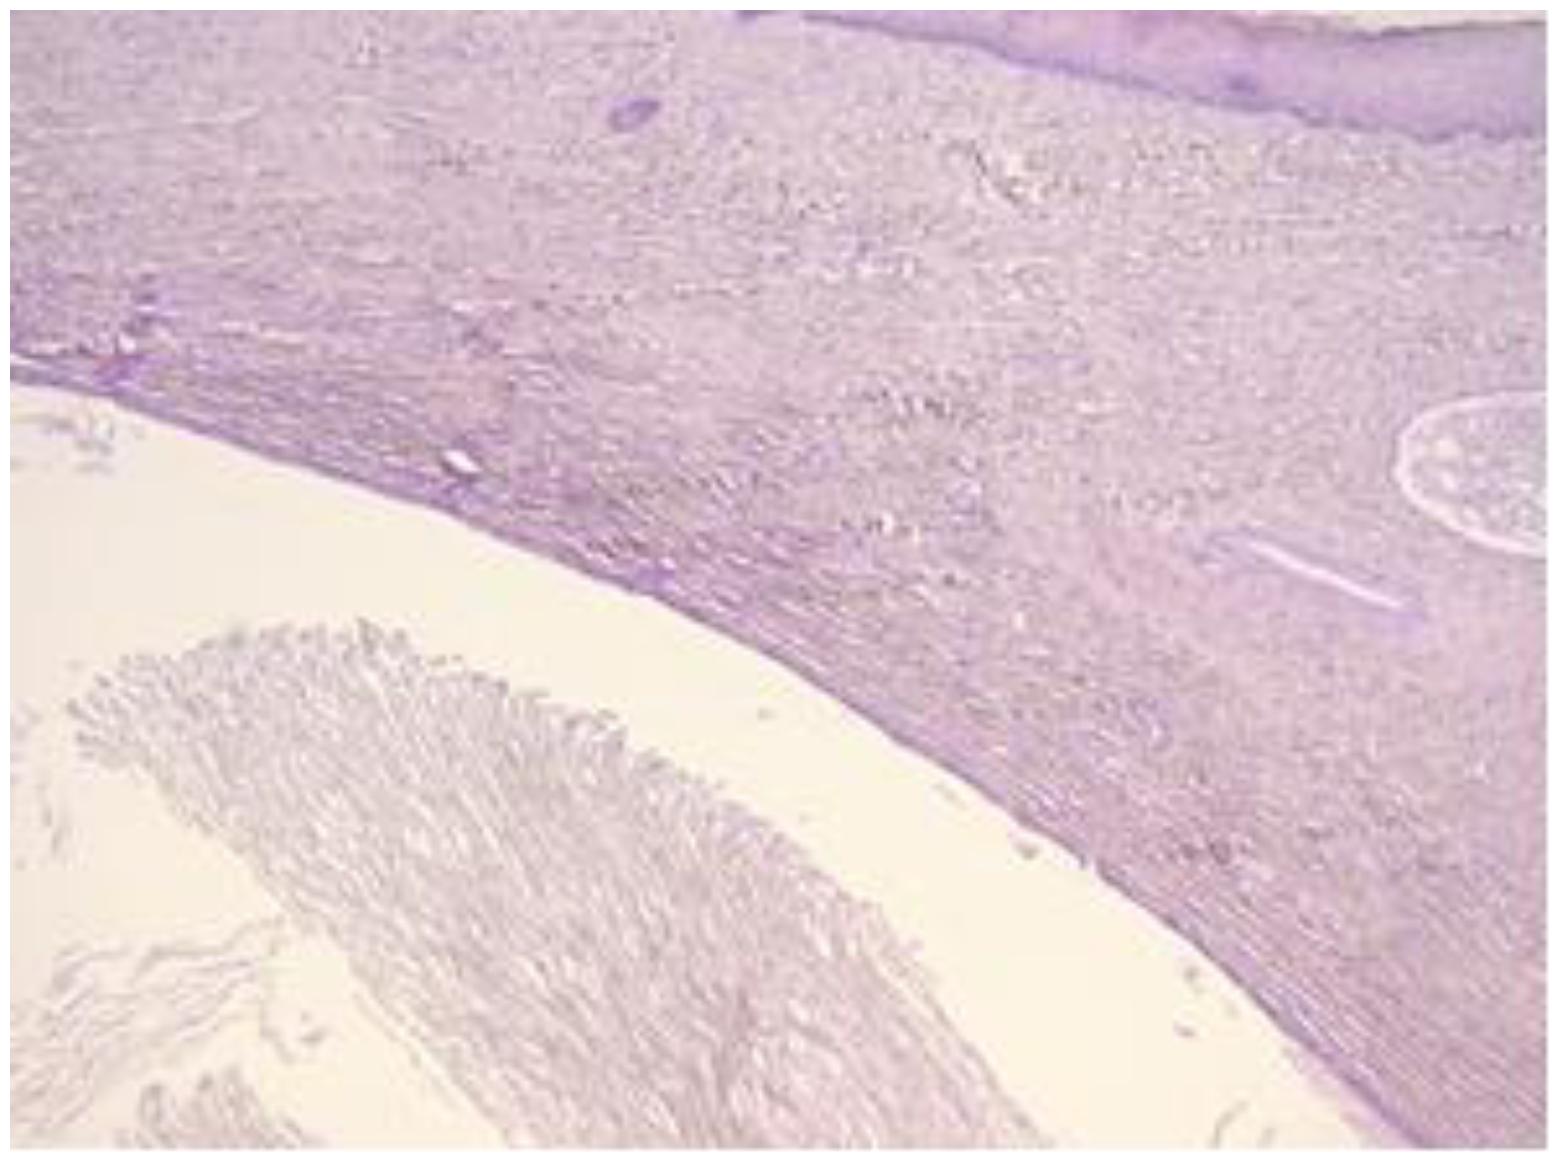

The exo-cervix shows a cystic structure in the deeper layers that is filled with an amorphic, eosinophilic, lamellar substance (Figure 3). The cyst is lined by stratified epithelium resembling squamous epithelium that reminds us of the typical structure found at the level of the endo-exocervical junction (Figure 4).

Figure 3. Exo-cervix shows a cystic structure in the deeper layers that is filled with an amorphic, eosinophilic, lamellar substance (HE staining, 5×).

Figure 4. Cyst is lined by a stratified epithelium that resembles a squamous epithelium, similar in appearance to the endo-exocervical junctional area (HE staining, 10×).